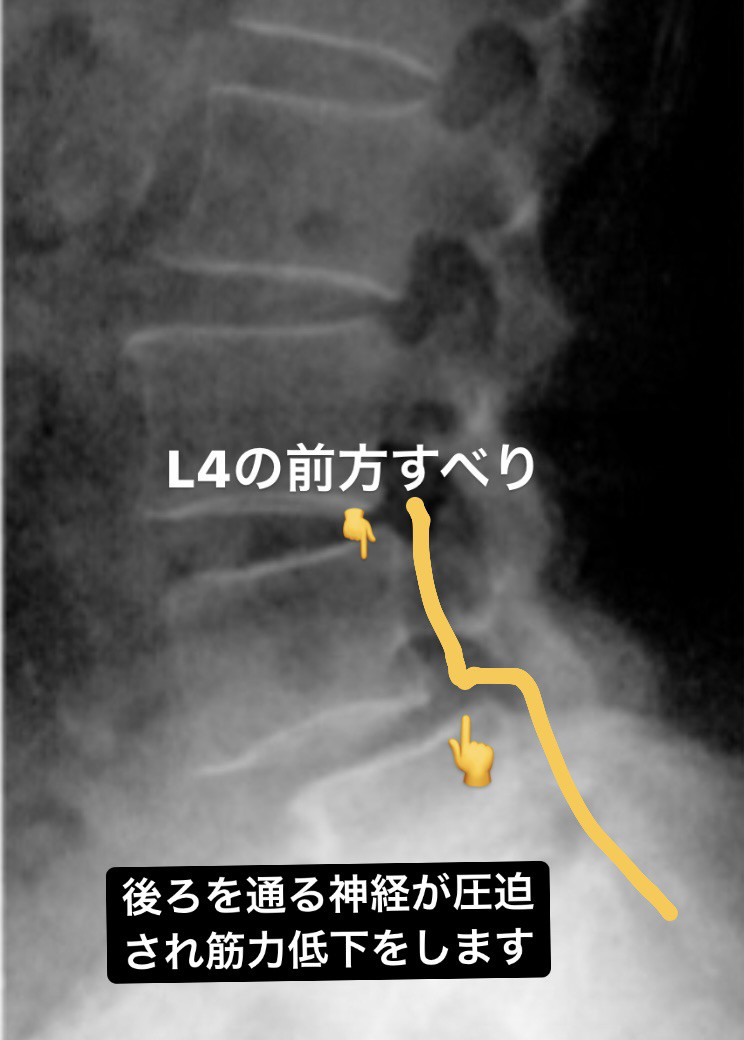

先日腰椎すべり症について書きましたが、すべり自体が根治することはないですが、症状を改善することができます。

すべり症とは腰椎が椎間板の変性などによって腰椎が前方に動いてしまうことで腰痛を引き起こしたり、脚に痛みやしびれ、筋力低下、感覚鈍麻などの神経症状が出ます。

4番目の腰椎がすべることが多く、腰を反ると腰痛を誘発します。立ち上がりの際、朝起きる時が痛いなどが患者さんの訴えとして多いのも特徴です。

腹筋群、骨盤底筋の筋力低下が続くと4番目の腰椎の前弯が強くなり椎間板が変性し腰椎が前方にすべるように移動します。

移動すると神経を挟み神経症状や腰椎が不安定になり腰を反らすと痛みが出ます。

神経症状が出ていても神経の通り道を確保し、体幹機能の改善、腰椎屈曲のストレッチをすると症状を改善することができます。